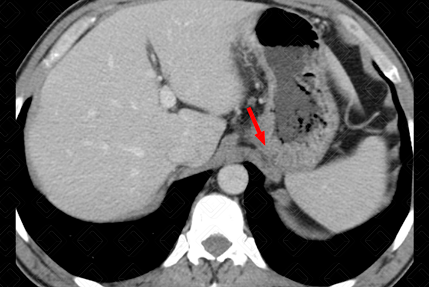

Descrição das figuras: Tomografia computadorizada do abdome pós-contraste, fase portal. Estadiamento de adenocarcinoma gástrico. Na seta vermelha, torna-se evidente o espessamento parietal da mucosa gástrica. As setas amarelas indicam linfonodomegalias em número aumentado na região perigástrica suspeitas.

• Tomografia computadorizada do abdome: Exame extremamente útil para estadiamento da doença, com avaliação da invasão local do tumor e, também, de metástases a distância. Permanece como exame de escolha para estadiamento pré-tratamento e para follow-up da lesão (figuras acima);